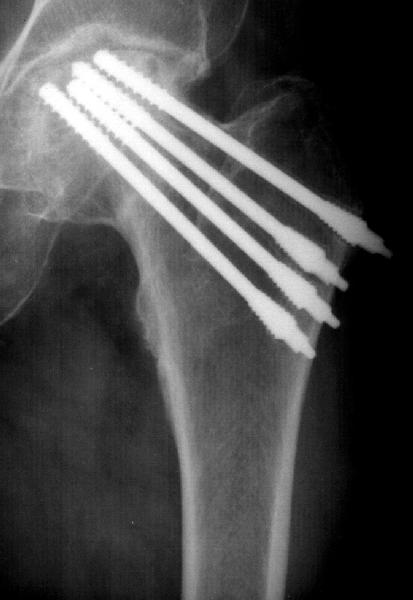

Коллеги из ортопедического отделения просят подсказать, что за фиксатор использован для остеосинтеза шейки бедра (см. приложение).Они собираются убрать их и сделать эндопротезирование, и хотелось бы знать, не потребуются ли какие-то нестандартные инструменты для удаления этих винтиков. Заранее спасибо.

Мне выглядит, что использовались натяжные спонгиозные шурупы Compression cancellous screws с дополнительной резьбой и шайбой для дополнительного затягивания шурупа и отломанной части головки к противоположному кортексу.Думаю не требуются никакие спец. инструменты для извлечения, только ручная и автоматическая головки для дрели.Обычно нет большого сопротивления выкручиванию. После удаления железа я бы подождал полгода или даже год до

Судя по снимку, это фиксаторы для перкутанного остеосинтеза (по методике проф. Шестерни). производит их известное вам предприятие ЦИТО, так что лучше уточнить там вопрос об инструментах.

Насколько мне известно, имплантация проводится с помощью специльных инструментов.

Evgueny Tchekashkine 27 Ноябрь 2002, 23:35

Фиксатор по форме напоминает Herbert screw , который мы используем для остеосинтеза переломов ладьевидной кости . Конструктивной особенностью этого типа фиксатора - противоположное направление резьб на проксимальном и дистальном отделах винта, что при введении винта приводит к межфрагментарной компрессии. Удаление таких фиксаторов дело совсем нелегкое даже при наличии оригинального инструментария так, как диаметр резьбы в проксимальном отделе превышает диаметр гладкой части винта, следовательно, при удалении придется *нарезать* резьбу в костном канале только в обратном направлении, что потребует приложения значительного усилия + прочного захвата дистальной части. Коль скоро планируется артропластика, то при возникновении проблем с удалением винтов можно сначала вывихнуть головку бедра, остеотомию шейки, разрушить головку бедра и вывинтить винты ретроградно.

Травматично, дополнительные затраты времени, но других вариантов я не вижу, если, конечно, первая попытка окажется безуспешной.